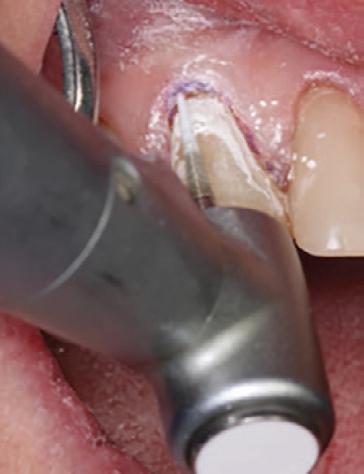

CLEARFIL MAJESTY™ ES Flow Universal in shade UD (Universal Dark) was paced in 0.5mm increments, with each layer light-cured prior to the next (Figure 7).

Approximately 3-4 layers were used to fully restore the lesion to its final contour. (Figure 8). The spherical fillers and light scattering properties of the flowable composite allowed for seamless shade integration with the surrounding enamel.

Finishing and Polishing

A fine-grit diamond bur was used to shape and finish the restoration (Fig. 9). Final luster was achieved using a twostep polishing system from Meisinger USA (Fig. 10). The retraction cord was removed at the end of the procedure.